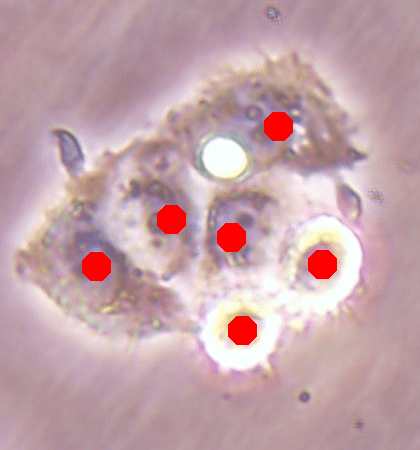

Before the advances in deep learning, the traditional approach for cell detection/segmentation is to employ low-level handcrafted features, reflecting color, edge, and shape characteristics of cells. This approach has given promising results when the features are defined properly, as a good representation of the visual cell characteristics. On the other hand, these characteristics may change from one cell type to another (see Fig. 1) and new features need to be defined to meet the cell characteristics of a new type. Additionally, when there exists heterogeneity in the visual characteristics of the same cell type, using a single model may not be sufficient to detect all cells of this type, particularly for cancer cells which are exploited more in high throughput screening.

![]() |

| (a) | (b) | (c) |

We test our DeepDistance model on three datasets, each of which consists of live cell images of a different cell line. They are the CAMA-1, MDA-MB-453, and MDA-MB-468 human breast cancer cell lines. The images in all datasets were acquired at magnification and pixel resolution. An example image from each dataset is shown in Fig. 1. As seen in this figure, cells might be visually different within and across different cell lines.